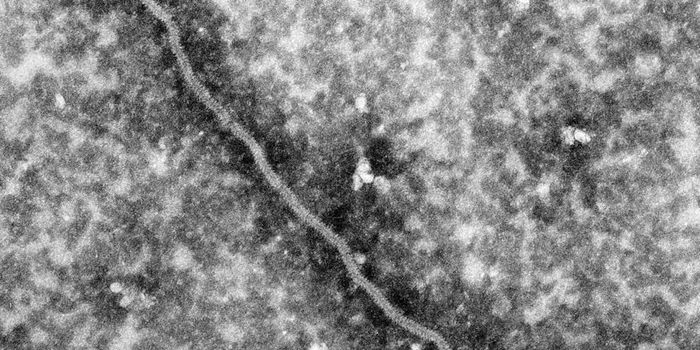

JAN 31, 2016Clinical & Molecular DXNo, you can’t catch Alzheimer’s like you could a cold. But new evidence suggests Alzheimer’s may be tr ...

JAN 14, 2016Clinical & Molecular DXAlzheimer’s disease is highly prevalent, accounting for over 7 million new cases every year. While there’s n ...

JAN 25, 2016Clinical & Molecular DXChronic exposure to an environmental toxin known as BMAA may significantly increase the risk of developing Alzheimer&rsq ...